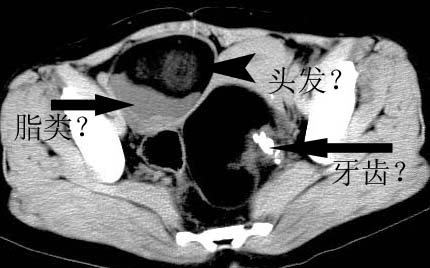

女性 病人 44岁 盆腔 下腹部痛1天!

盆腔内低密度为主混杂等密度及少许囊样与班状钙化影,如果做了肠道准备就好了。支持畸胎瘤。当然做mri会更好

典型的双侧附件畸胎瘤.

支持各位大侠观点.病人有急性腹痛,需除外有扭转可能.建议mri.